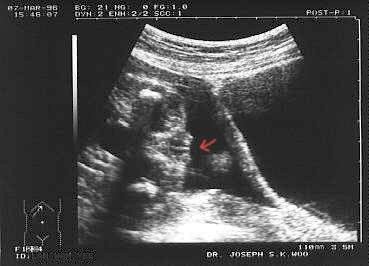

Posílám dva snímky, červenou šipkou je označeno pohlaví (děvče, chlapec).

Ženské pohlaví